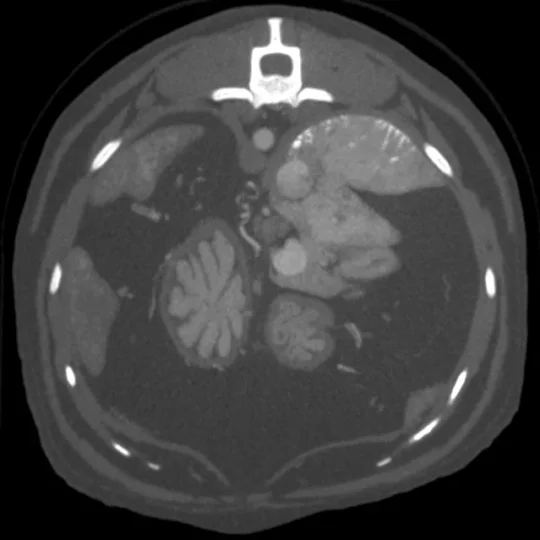

Tomografia komputerowa (TK) to nowoczesne, zaawansowane, bezinwazyjne i bezbolesne badanie diagnostyczne, które stanowi istotne uzupełnienie innych metod obrazowania, takich jak klasyczne RTG czy ultrasonografia. Dzięki wykorzystaniu w naszej klinice technologii TK możliwe jest uzyskanie precyzyjnych, trójwymiarowych obrazów wnętrza organizmu, co znacznie zwiększa skuteczność diagnostyki i pozwala na dokładniejszą ocenę stanu zdrowia pacjenta.

Tomografia komputerowa opiera się na serii ekspozycji promieniowania rentgenowskiego wykonywanych pod różnymi kątami. Uzyskane dane są następnie przetwarzane przez zaawansowane oprogramowanie komputerowe, które tworzy trójwymiarowy obraz badanej okolicy. W przeciwieństwie do tradycyjnego RTG, gdzie struktury nakładają się na siebie, TK pozwala na precyzyjne zobrazowanie poszczególnych warstw anatomicznych, co znacznie poprawia jakość diagnostyki.

- w niektórych przypadkach także tkanek miękkich (np. mózg, narządy jamy brzusznej, guzy nowotworowe, zmiany zapalne).

Środek kontrastowy W celu uzyskania jeszcze bardziej szczegółowych obrazów często stosuje się środek kontrastowy na bazie jodu. Kontrast podawany jest dożylnie lub bezpośrednio do określonych przestrzeni ciała (np. przestrzeń podpajęczynówkowa, kanały słuchowe, stawy, drogi moczowe), co umożliwia dokładniejszą ocenę struktur, które w standardowym badaniu mogłyby pozostać niewidoczne.